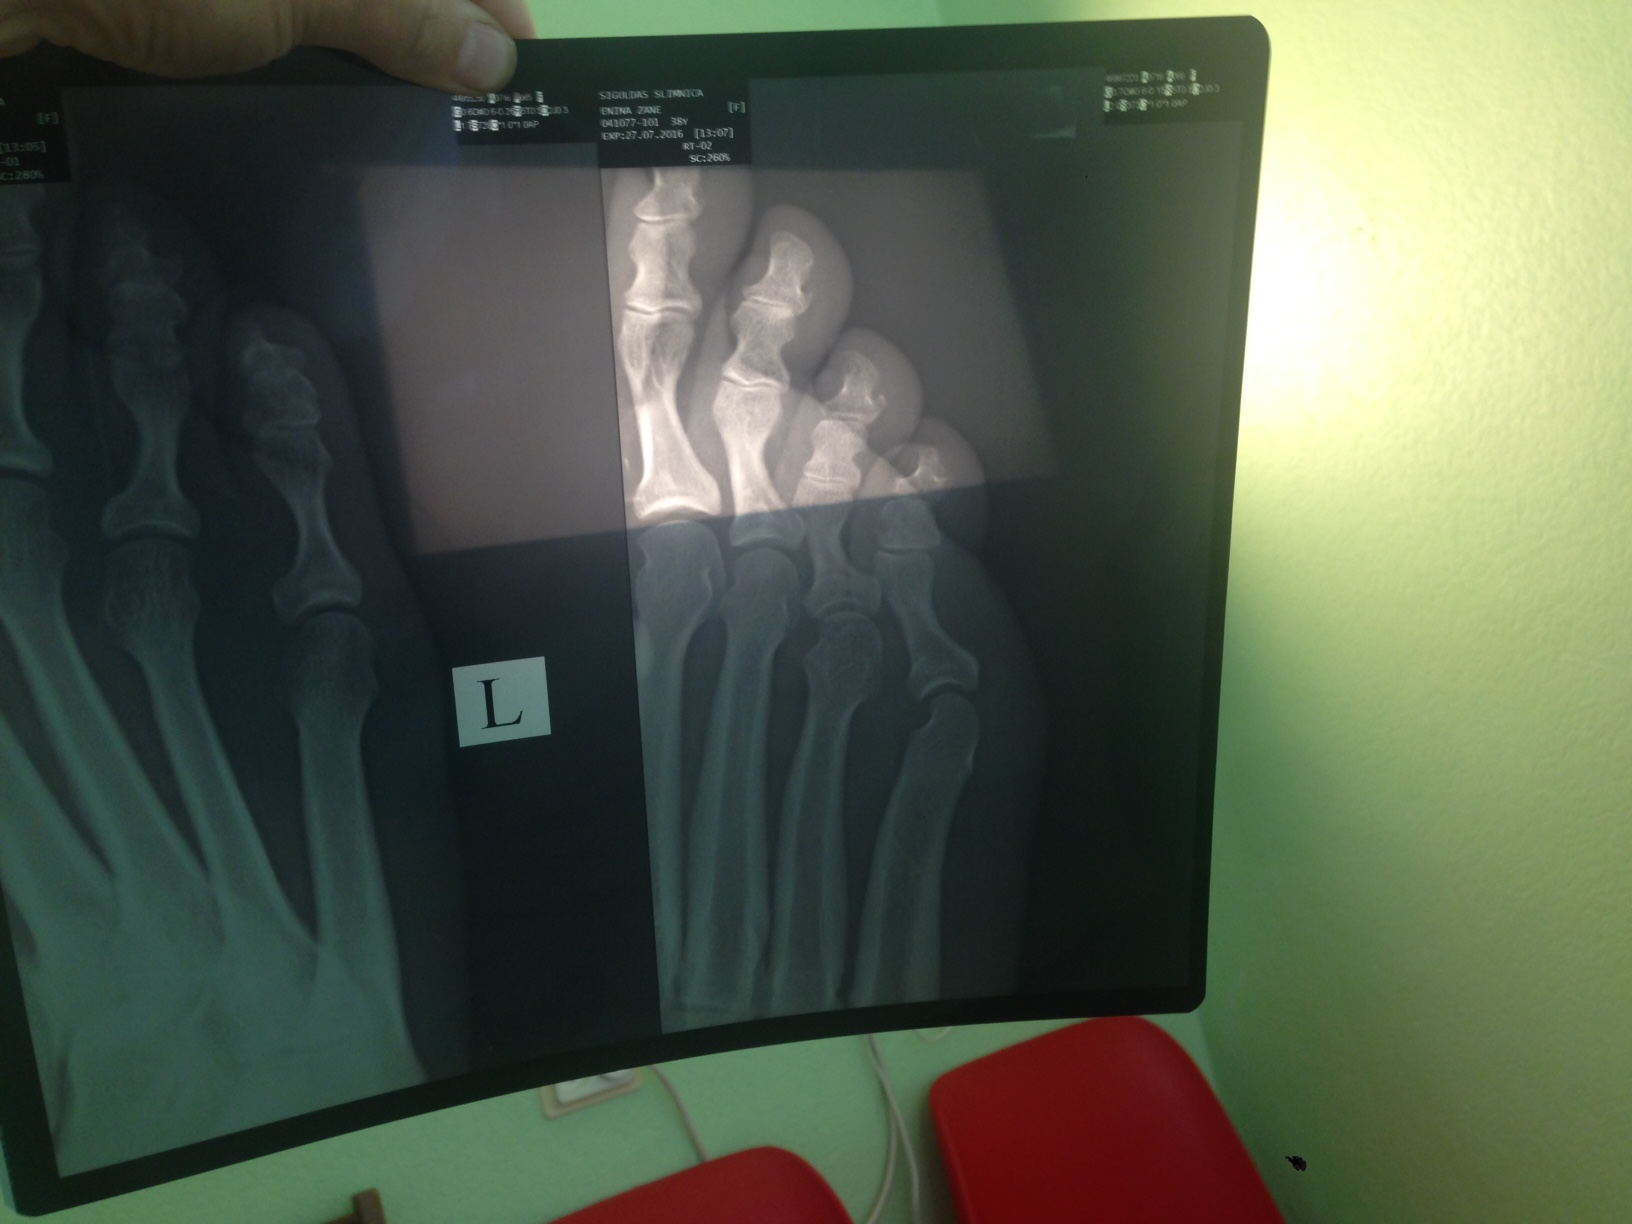

No rīta mazais pirkstiņš izskatās kā melleņu draudziņš, neganti sāp un visādi citādi signalizē, ka būs salūzis. To apstiprina arī rentgens un daktere, kura izsaka cerību, ka dīvānam gan viss kārtībā.